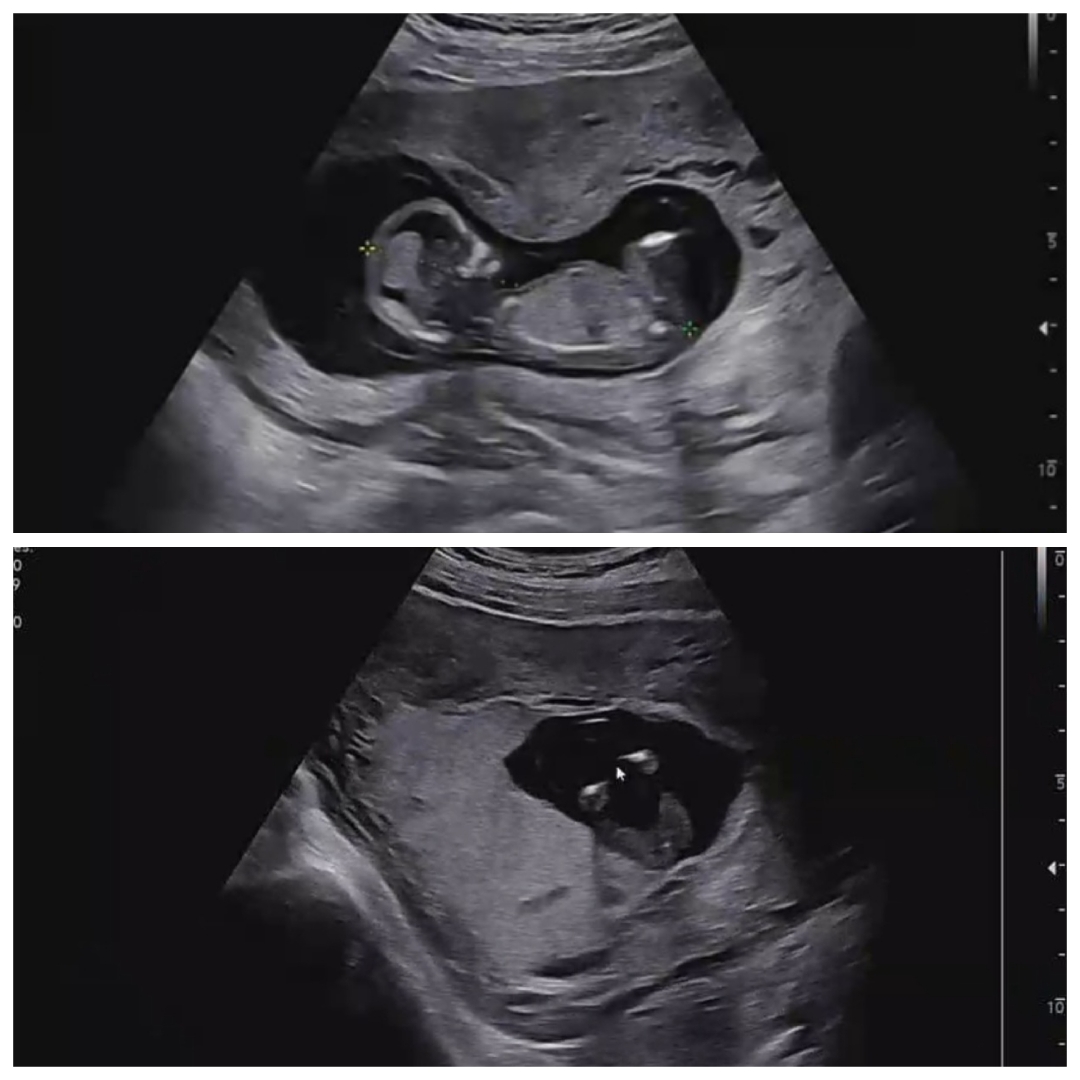

13주차, 1차기형아 검사하고왔어요

초음파보다 성별이 궁금해서 여쭤봤더니, 이제 생식기가 만들어 지고있는시기라.. 성별을 알려주기 이르다고 하시더라구요;; 근데 초음파를 보는데, 엉덩이 밑을 비추시는데.. 다리사이가 매끈하더라구요?? 시간이 더 지나면, 다리사이 아무껏도 안보이던게 보일수 있는건가요???